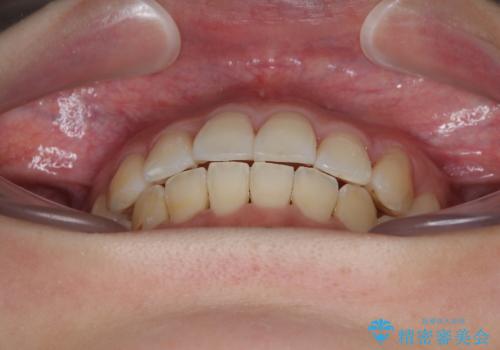

- 上下前歯のデコボコを気にして来院された患者様です。

上顎歯列が下顎の歯列に対して狭小であり、一部下顎の奥歯が上顎よりも外側に位置している状態でした。

上顎の拡大は、左右どちらに拡大していくのか予想が困難ですが、こちらの患者様では結果として上下正中が一致する方向に拡大され、非常にきれいな仕上がりとなりました。